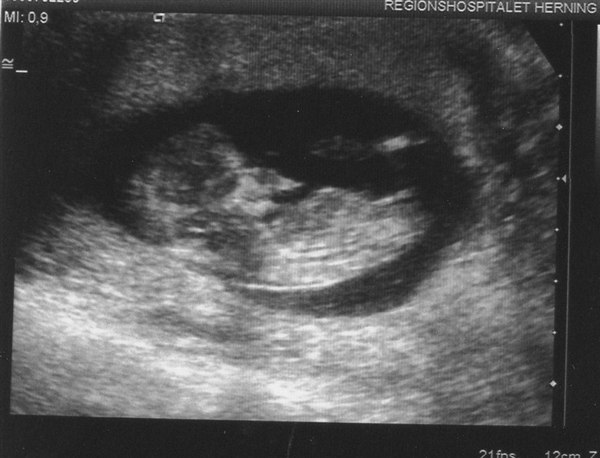

Her er vores lille bebs

Vedhæftede fotos (klik for at se i fuld størrelse)